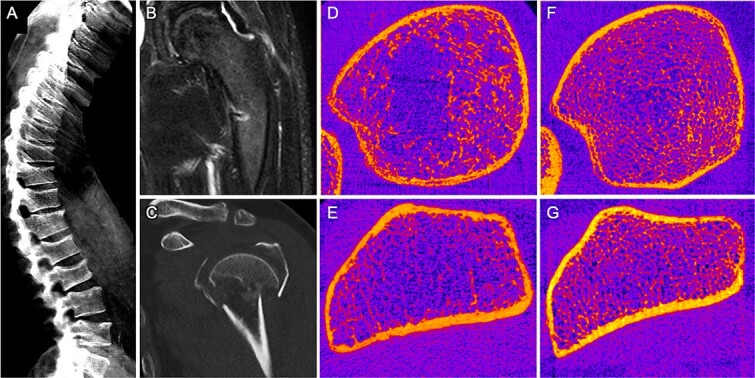

缺铁性贫血可以通过补充铁来治疗。越来越多的证据表明,铁输注中的碳水化合物成分可导致低磷血症和随后的骨软化,这是由于过量的完整成纤维细胞生长因子23 (iFGF23)。我们在此对13例铁输注诱导的骨软化症(IIIO)患者进行了深入的表征。通过实验室、骨密度、HR-pQCT和虚拟类骨体积估计对患者进行特征描述(单中心机构实践)。我们还报告了一位患者,他接受了布若单抗治疗,因为尽管有骨软化症,但必须继续输注铁。13例患者均接受三羧基麦芽糖铁(FCM)输注,均出现低磷酸盐水平。停止FCM输注和替代磷酸盐、钙、天然和/或活性维生素D的支持治疗是所选择的治疗方法。疼痛、活动能力和生化数据,如血清磷酸盐水平、骨密度、骨微结构和虚拟类骨体积是主要的结局指标。我们的结果表明生化正常化(例如,磷酸盐水平前:0.50 mmol/L±0.23 mmol/L,后:0.93 mmol/L±0.32 mmol/L, ppre: 7.31±1.22,VASpost: 2.73±1.27,ppre: -1.85±1.84,T-scorepost: -0.91±2.13,p

Iron deficiency anemia is treated by iron supplementation. Increasing evidence has shown that the carbohydrate components in iron infusions can cause hypophosphatemia and subsequent osteomalacia due to excess intact fibroblast growth factor 23 (iFGF23). We here undertook an in-depth characterization of 13 patients with iron infusion-induced osteomalacia (IIIO). Patients were characterized (monocentric institutional practice) by means of laboratory, bone density, HR-pQCT, and virtual osteoid volume estimation. We additionally report a patient who was treated with burosumab because iron infusions had to be continued despite osteomalacia. All 13 patients received ferric carboxymaltose (FCM) infusions and presented with low phosphate levels. Stopping the FCM infusions and supportive treatment by substitution of phosphate, calcium, native, and/or active Vitamin D was the chosen therapeutic approach. Pain, mobility, and biochemical data, such as serum phosphate levels, BMD, bone microstructure, and virtual osteoid volume, were the main outcome measures. Our results indicate biochemical normalization (eg, phosphate levels pre: 0.50 mmol/L ± 0.23 mmol/L, post: 0.93 mmol/L ± 0.32 mmol/L, p<.001) after stopping the FCM infusion and establishing supportive treatment. Additionally, pain levels on the visual analog scale (VAS) decreased (VASpre 7.31 ± 1.22, VASpost 2.73 ± 1.27, p<.0001) and areal BMD (expressed by T-score) improved significantly (T-scorepre: -1.85 ± 1.84, T-scorepost: -0.91 ± 2.13, p<.05). One patient requiring ongoing FCM infusions experienced significant additional benefits from burosumab treatment. In conclusion, our results highlight the importance of monitoring phosphate in patients treated with FCM infusions. Stopping FCM infusions is effective in addressing the excess of iFGF23 and thereby phosphate wasting. Supportive therapy enables quick recovery of the musculoskeletal system and improves pain levels in these patients.